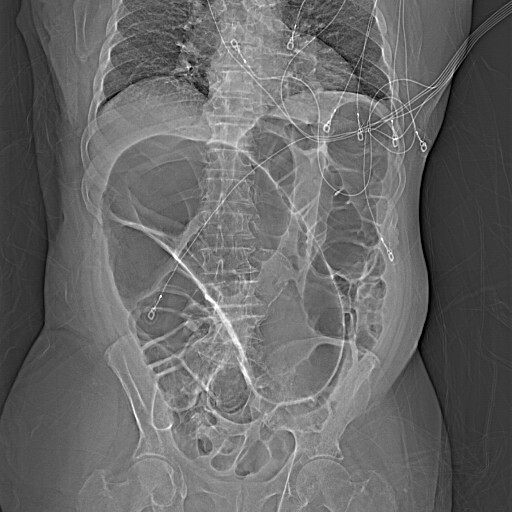

A 99-year-old man presented to the hospital with four days of progressive abdominal pain and distention accompanied by anorexia and obstipation. Examination revealed a markedly distended, tympanitic abdomen with hypoactive bowel sounds and diffuse tenderness. An abdominal radiograph showed markedly dilated loops of large bowel shaped like a coffee bean (Figure 1). Computed tomography (CT) of the abdomen and pelvis confirmed a severe dilation of the sigmoid colon with twisting of the sigmoid mesocolon and vessels consistent with sigmoid volvulus (Figure 2). The patient underwent flexible sigmoidoscopy for endoscopic decompression and ultimately required colectomy for recurrent sigmoid volvulus.

While plain radiographs readily detect sigmoid volvulus, CT confirms the diagnosis in most cases through identifying mesenteric twisting.2 Colonic dilation without twisting or a mechanical obstruction suggests a diagnosis of ACPO. Cecal volvulus may present similarly on abdominal radiography but typically demonstrates only a single air-fluid level, in contrast to the two air-fluid levels often seen in sigmoid volvulus.1 CT imaging is likewise necessary for distinguishing between cecal and sigmoid volvulus. Clinicians should carefully review the radiograph and CT images for pneumatosis intestinalis, which suggests arterial ischemia, and pneumoperitoneum, which indicates bowel perforation, both of which constitute surgical emergencies.2